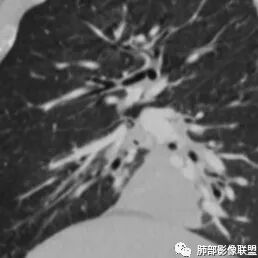

琦遇:好病例!支气管爬行;右肺中叶有树芽征;右侧分支支气管壁弥漫性增厚了。右肺下叶内基底段支气管通而不畅。

尘缘:患者炎性指标高,有支气管爬行征,支气管壁增厚,未完全堵塞,有点仙人掌的味道,而且纵隔脂肪间隙虽然模糊,但无明显肿瘤样强化。所以肯定先排查结核。所以用任何一种肿瘤都不好全部解释的,最先要排查的就是结核。

(1)病灶形态和分布:双肺散在点片影,可见树芽征。右肺下叶内基底段实性密度团块状影,底部坐落膈面、浅分叶,略呈圆锥形沿血管支气管束探及肺门,可疑“支气管爬行征”。奇食窝区分出子灶。病灶轻中度强化不均,斑片状低密度无强化区,疑坏死,未见钙化。右肺门及淋巴结肿大。

(2)支气管和血管:右肺支气管分支管壁弥漫性增厚,中间段支气管散在结节样凸起,右肺下叶内基底段支气管闭塞,但远端可疑复出。余病灶围绕支气管腔内远端无明显阻塞性不张。内部血管走形自然,提示包绕为主。

●  【肺部影像征象精粹系列】支气管树爬行征详解

●  【肺部影像病理系列】支气管针孔征!

●  【肺部影像病理系列】支气管改变及"小花小草"等疾病谱延伸